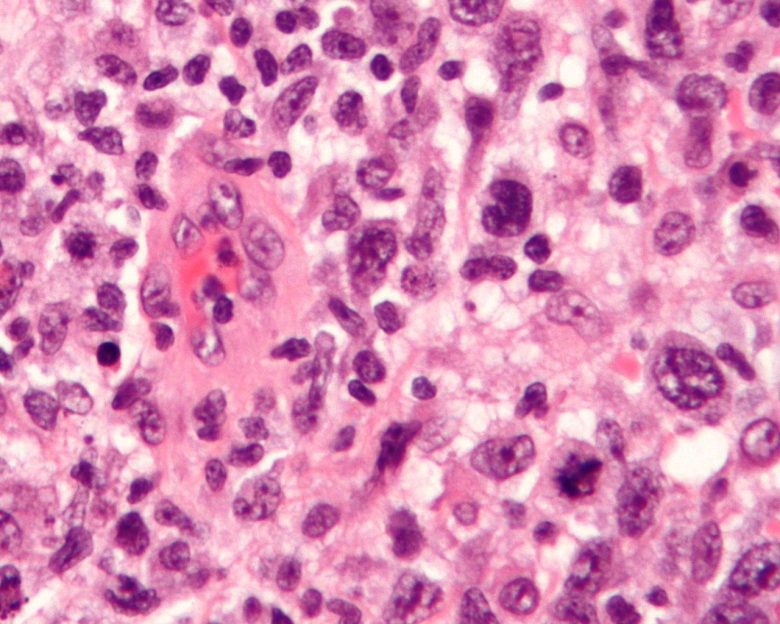

Image Credit: Nephron / Wikimedia Commons.

Bladder cancer

“The most common type of bladder cancer is transitional cell carcinoma, also called urothelial carcinoma. Smoking is a major risk factor for bladder cancer. Bladder cancer is often diagnosed at an early stage. For more information, view bladder cancer symptoms, tests, prognosis, and stages.”